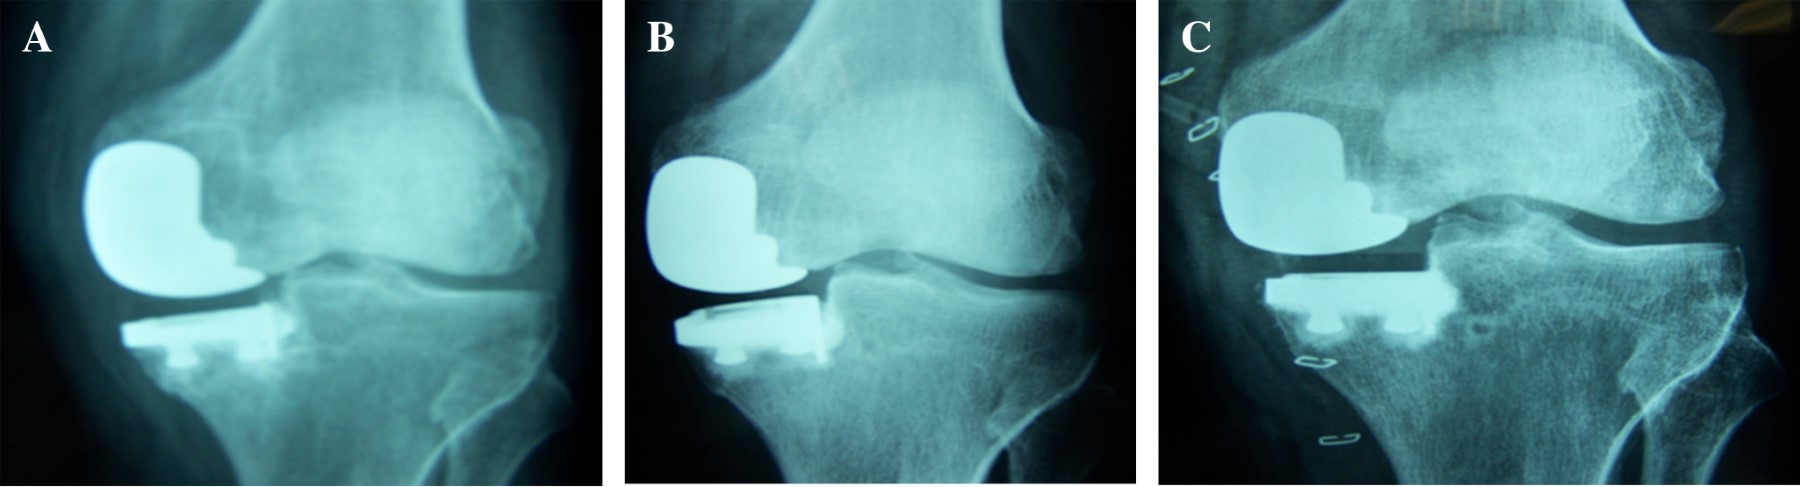

Al decir que los resultados han mejorado por los progresos de los implantes, es porque existen dos líneas que tienen un largo seguimiento. La de platillo móvil de la Escuela de Oxford donde el concepto es que disminuye el desgaste y la producción de partículas al poder disminuir la fricción en un punto o una línea fija de la superficie del inserto. A pesar de que algunos trabajos experimentales han demostrado que el número de partículas no es menor que en las fijas, la supervivencia de los implantes es lo suficientemente larga como para obtener resultados comparables con las de platillo fijo (Figura 4). Estas últimas tienen la ventaja de casi no correr el riesgo de que se luxe el plástico y que, por lo mismo, se puedan ocupar en el compartimiento lateral, más móvil sin inconvenientes. Pero tendrían menos margen para tolerar una posición más allá de lo recomendado en cuanto a la fricción que ocurriría sobre el plástico, que en las de inserto móvil.